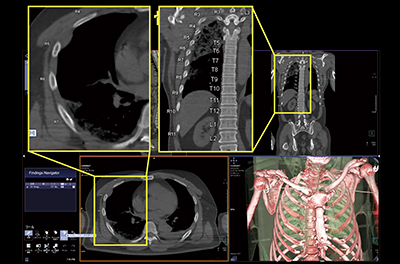

さらに今後,臨床活用が期待されるsyngo.viaの機能として,体幹部CTの読影支援機能がある。骨病変の評価を行う“CT Bone Reading”は,CTのthin sliceデータがsyngo.viaに送信されると,骨の読影支援機能が働き,肋骨などを1本ずつナンバリングする。これにより,どの骨を観察しているのかを把握しながら読影を行うことができ有用である(図5)。また,肋骨を左右に広げたような画像を作成でき,1本の肋骨に2か所の骨折があるような場合も観察が容易となる(図6)。外傷患者の緊急検査を行う場合,検査前にCT Bone Readingを設定しておくことで撮影後すぐに処理が行われ,速やかに読影できる。

図5 CT Bone Readingの自動ナンバリングと自動作成のVR画像

図6 CT Bone Readingによる骨折の観察